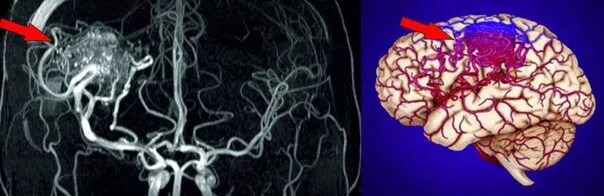

Мальформация сосудов